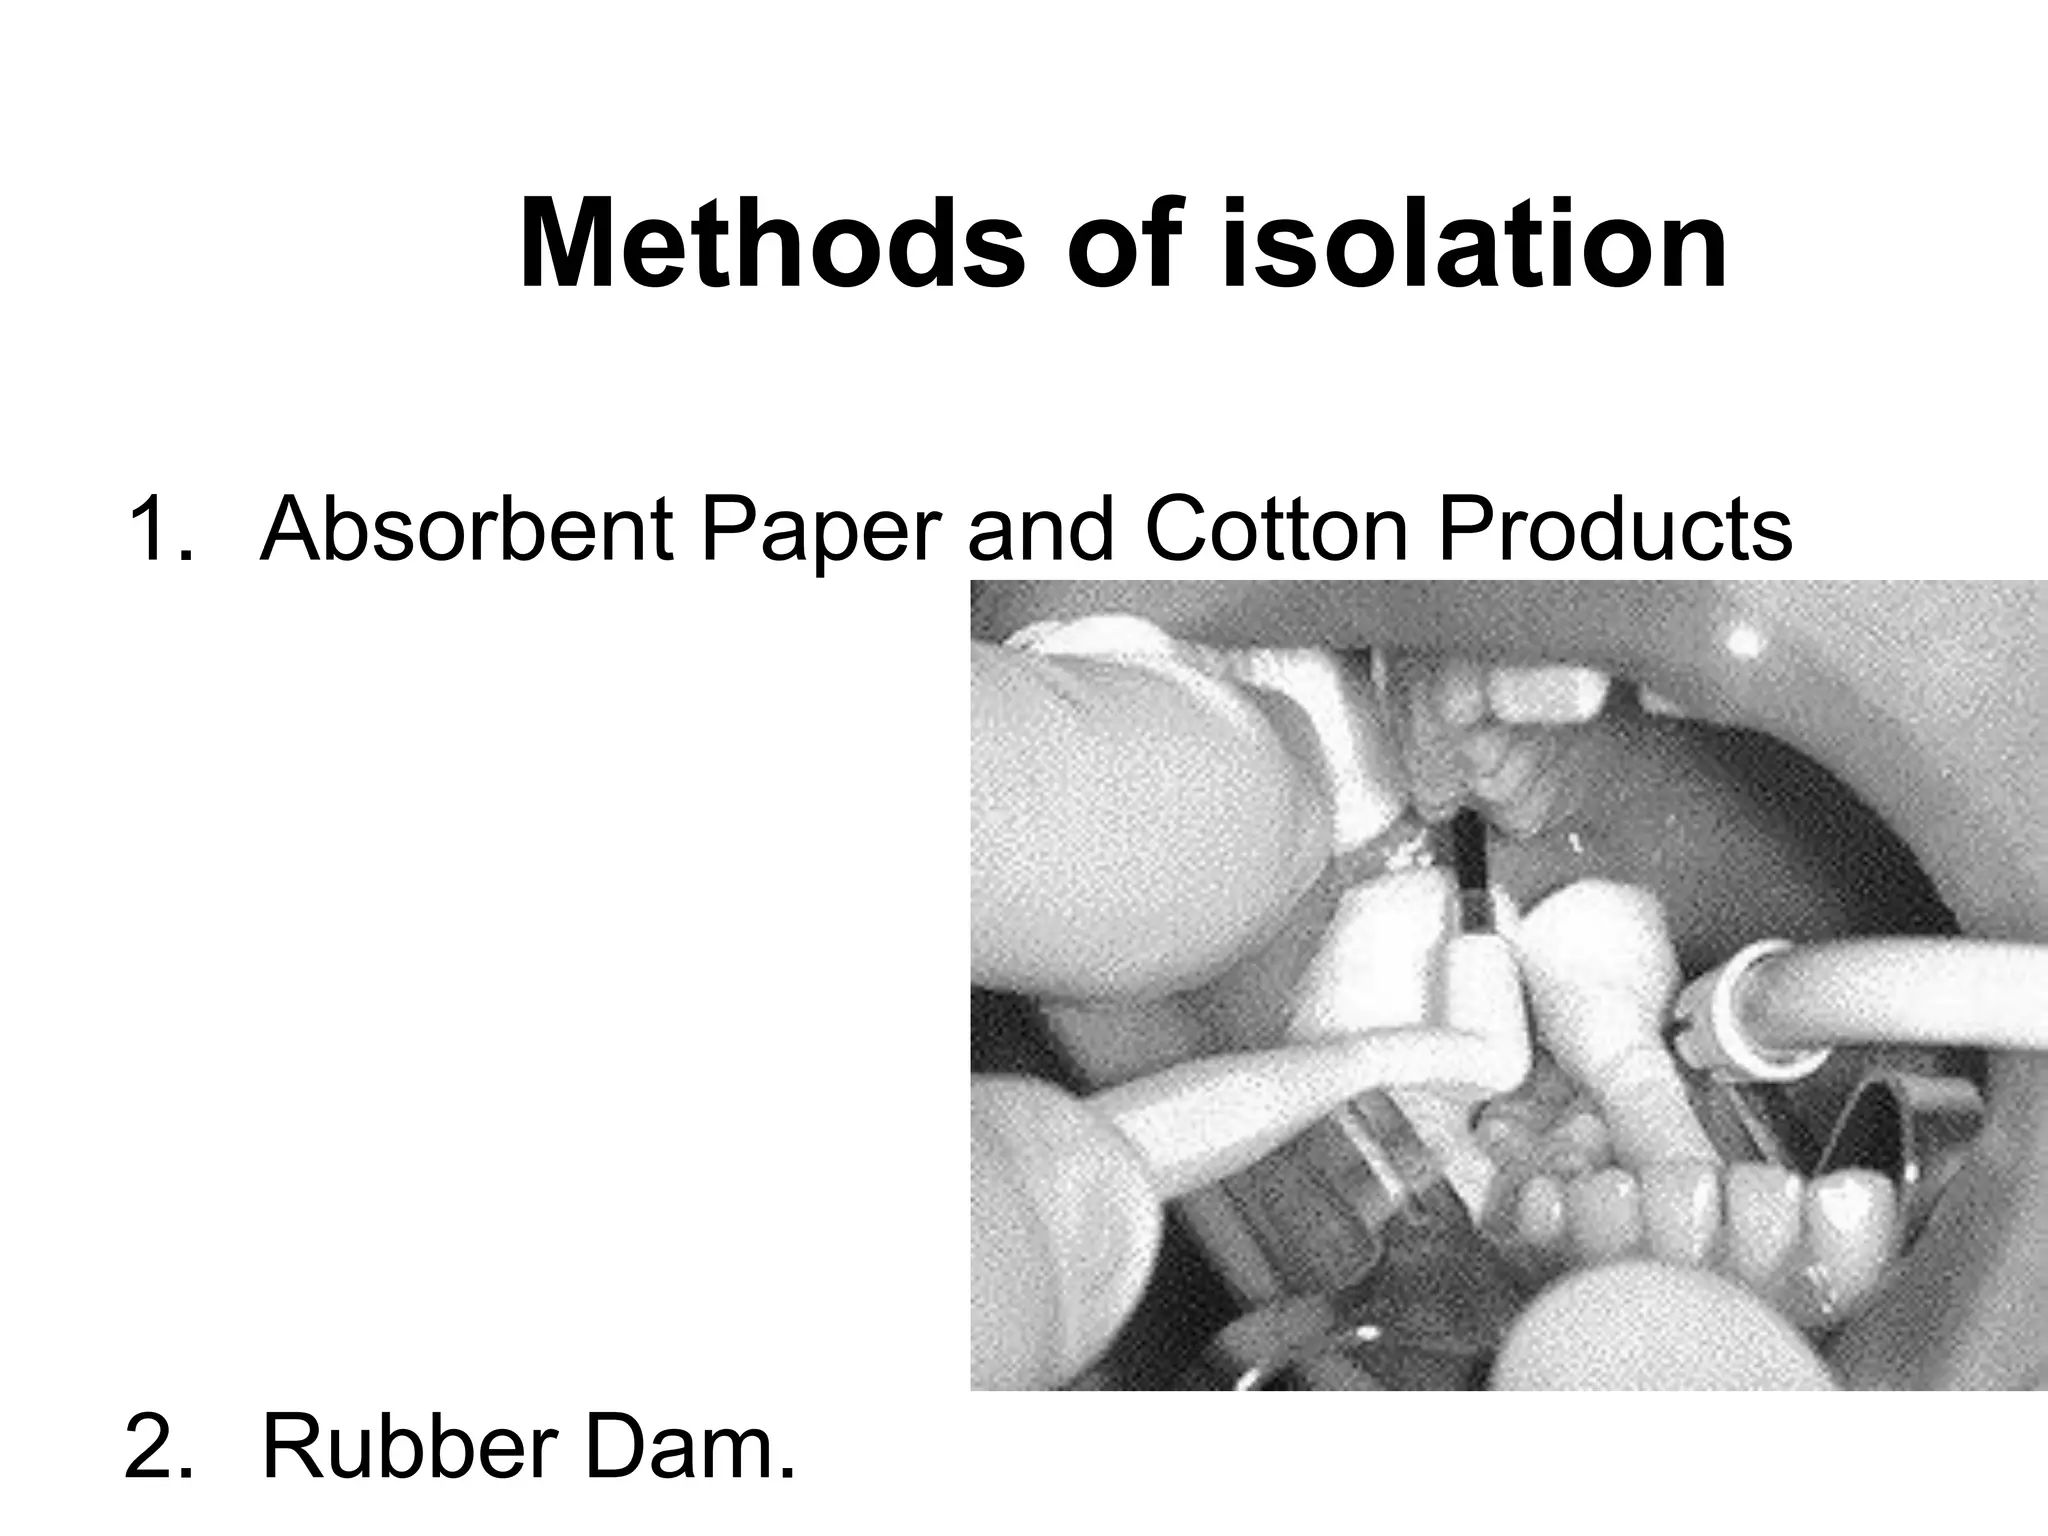

This document discusses the materials and components used for rubber dam isolation in dentistry. It describes the different types of rubber dam materials including color options and napkins to absorb moisture. It also outlines the tools needed such as punches to make holes, templates and stamps to guide hole placement, clamps to secure the dam, and other accessories like wedges and lubricant. Finally, it provides guidance on punching holes for different types of teeth and properly placing clamps in the rubber dam.